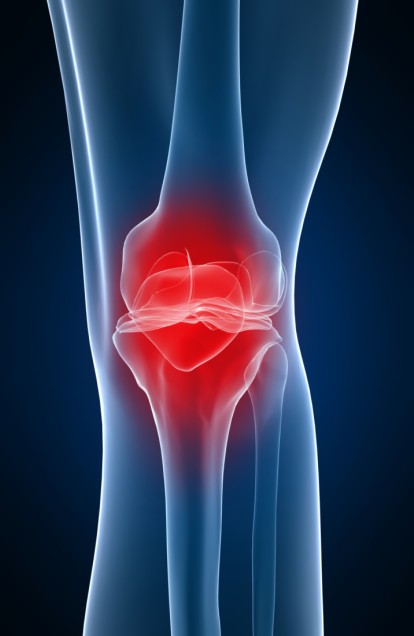

When choosing topics for Scientifically Speaking, I find it helpful to investigate everyday issues I see in my own health and the health of those around me. As an avid runner, I’m often running on the treadmill to get in a good cardio workout. And while I love running, lately I’ve noticed some joint pain, mostly in my knees and hips. It’s a little defeating to have this issue when running is your go-to exercise. So I did some digging and came up with a few simple tips to share for helping and maintaining joint health.

What are Joints?

Before we get into the details, it’s important to understand exactly what a joint is and how it works.

Before we get into the details, it’s important to understand exactly what a joint is and how it works.

There are 206 bones in the average adult body, and all but one are joined to at least one other bone. It’s not like a bone resting directly against another one either — they need protection. This protection comes from our joints, which act as a meeting point or cushion between our bones.

Synovial joints, or moving joints, are highly engaged during exercise. They account for 90 percent of all joints in the body, and they’re made up of bone, cartilage, tendons, ligaments, and synovial fluid. Synovial fluid is important because it helps to increase cartilage density and elasticity along with protecting your body from infection and inflammation.

You can see that joints actually serve a huge purpose, which is why it’s important to take action now and start taking care of them.